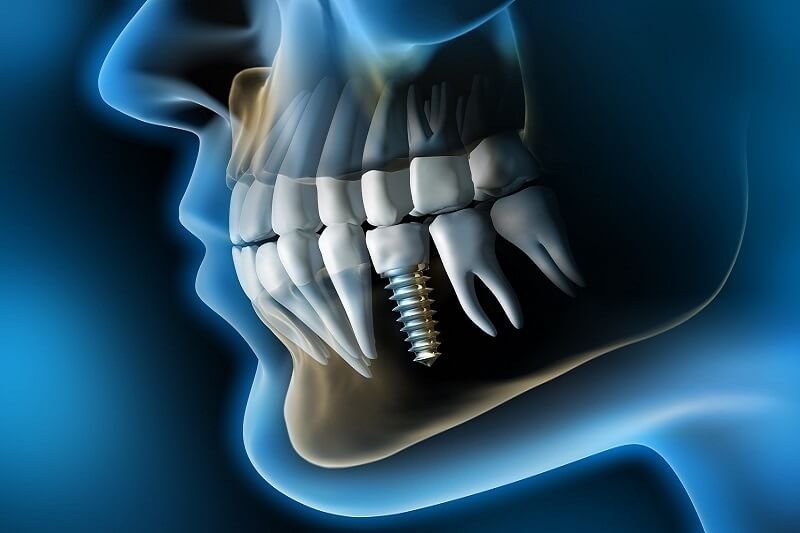

Endodoncja, jest zwana inaczej zabiegiem kanałowym. Jest to niezwykle złożone leczenie, które wykonuje się, jeżeli została uszkodzona miazga zęba.JAK PRZEBIEGA ZABIEG WSZCZEPIENIA IMPLANTU ZĘBOWEGO?

Implantacja stomatologiczna jest jedną z najskuteczniejszych i najbardziej komfortowych w późniejszym użytkowaniu, form uzupełniania braków zębowych.RTG ZĘBÓW A CIĄŻA

- implantologia